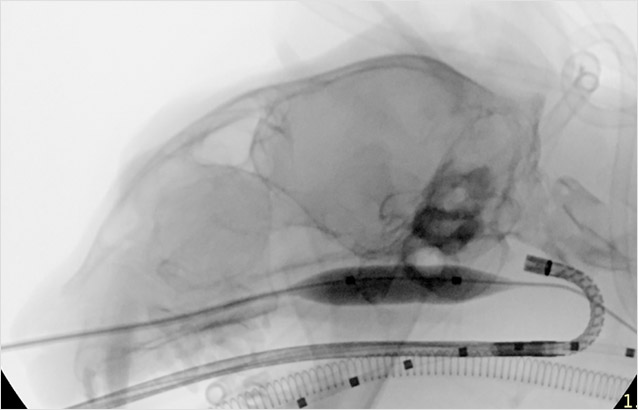

화학색전물질 주입 영상

간동맥 화학색전술 (Liver DEB-TACE) 시술 영상